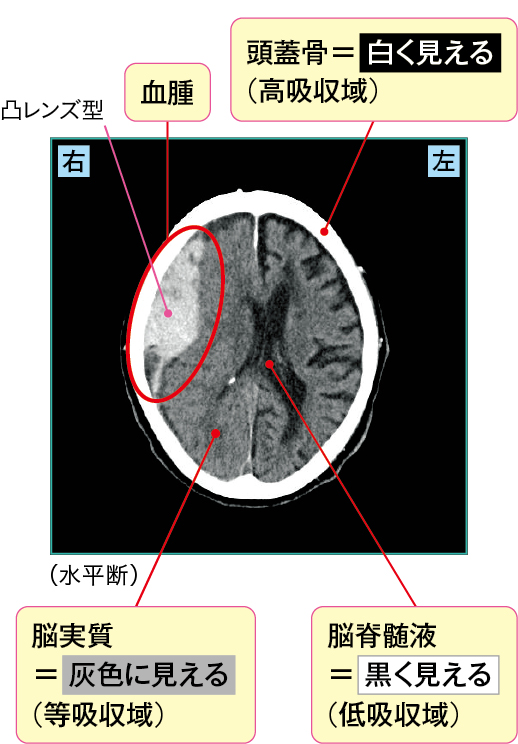

硬膜外血腫・硬膜下血腫の画像の見かた

1)急性硬膜外血腫

急性硬膜外血腫は、頭部外傷により硬膜にある硬膜動脈が破れて出血し、頭蓋骨と硬膜の間に血腫ができたものです(図2-1)。

頭部CT画像では、外傷を受けた部位を中心とした凸レンズ型の高吸収域が見られるのが特徴です。

図2 急性硬膜外血腫(CT)

急性硬膜外血腫のCT画像

出血源は中硬膜動脈が多く、ほかにも椎間静脈の損傷等でも急性硬膜外血腫が生じやすいとされます。

受傷直後は脳震盪により意識障害が出現しやすいでしょう。その後、一時的に意識が回復する意識清明期を経ますが、徐々に血腫が増大し、脳幹が圧迫されるために再び意識障害が生じます。

そのほかにも、血腫増大により頭蓋骨の内側の圧が高まると、脳が圧迫され受傷部位と反対側の片麻痺や、硬膜や脳血管に存在する痛覚が刺激され頭痛が生じます。また、延髄にある嘔吐中枢が圧迫されることで悪心嘔吐を生じることもあります。

図2の症例では血腫により脳が圧迫され、左上下肢麻痺が出現していました。